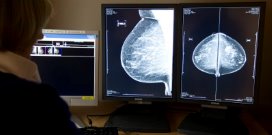

Screening op borstkanker heeft er niet toe geleid dat de sterfte aan borstkanker in enkele West-Europese landen sinds 1990 is gedaald. Tot die conclusie komt een onderzoeksgroep onder leiding van Philippe Autier van het International Prevention Research Institute in Lyon in een artikel in British Medical Journal.

De trends in sterftecijfers variëren nauwelijks tussen landen waar vrouwen al heel lang op borstkanker worden gescreend en landen waarin dat in een belangrijk deel van de onderzochte periode niet gebeurde. In Nederland, waar screening in 1989 begon, daalde de sterfte met 25 procent, nauwelijks meer dan in Vlaanderen, dat pas in 2001 met screening begon (24,6 procent). Tussen Zweden (1986, 16 procent) versus Noorwegen (1996, procent) is het verschil zelfs andersom dan je zou verwachten. Tussen Noord-Ierland (het Verenigd Koninkrijk begon in 1990 met borstkankerscreening) en Ierland (2000) is het verschil in daling klein: 29,6 versus 26,7 procent.

Volgens de onderzoekers zijn de dalende sterftecijfers vooral te danken aan verbeterde behandelmogelijkheden en een efficiënter systeem van gezondheidszorg.